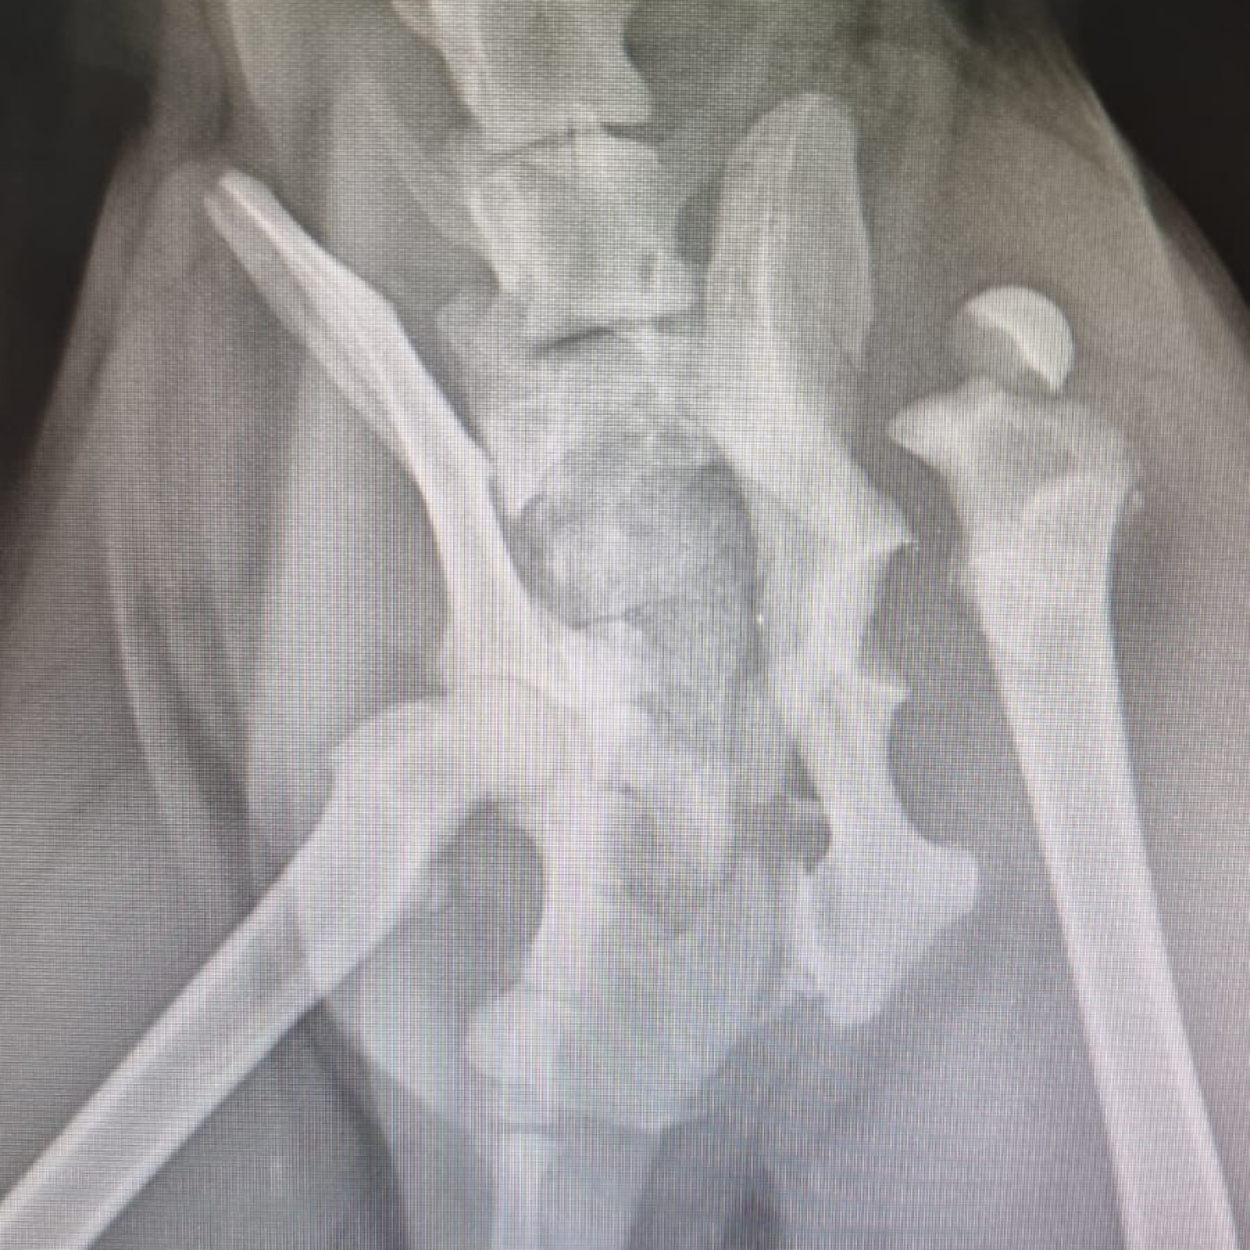

Hope konnte geröntgt werden. Was man nun sieht, tut einem schon vom hinsehen weh...

Das Gute: mit den Bildern wissen wir nun, was genau los ist und dementsprechend, was zu tun ist.